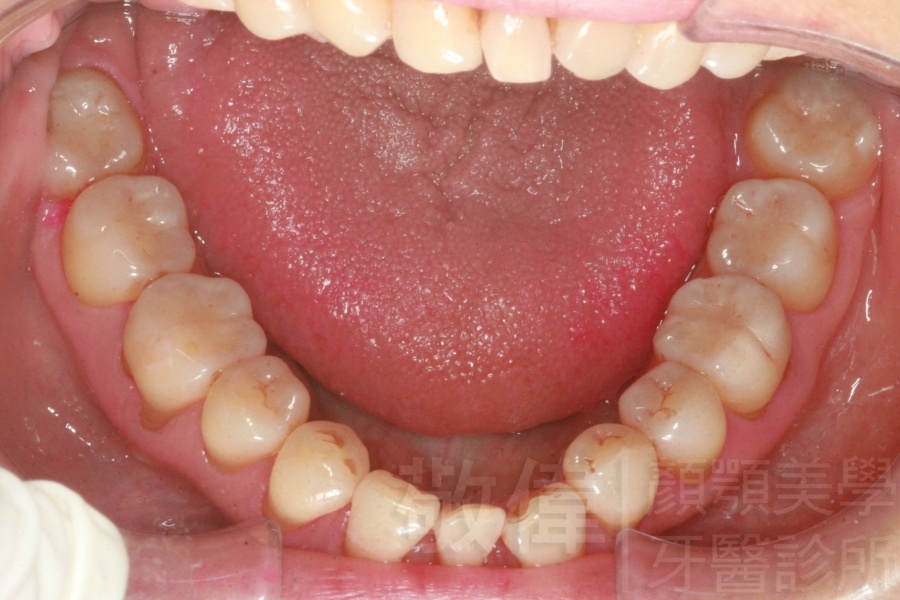

矯正前-上   矯正前-下

矯正後-上   矯正後-下

<個案說明>

上下暴牙嘴唇不容易合起來,經矯正完成後,嘴唇很容易合起來。在學生時期的時候的他,舉止之間充滿著有自信,當時還參加了舞蹈社團,充滿了多采多姿的生活。